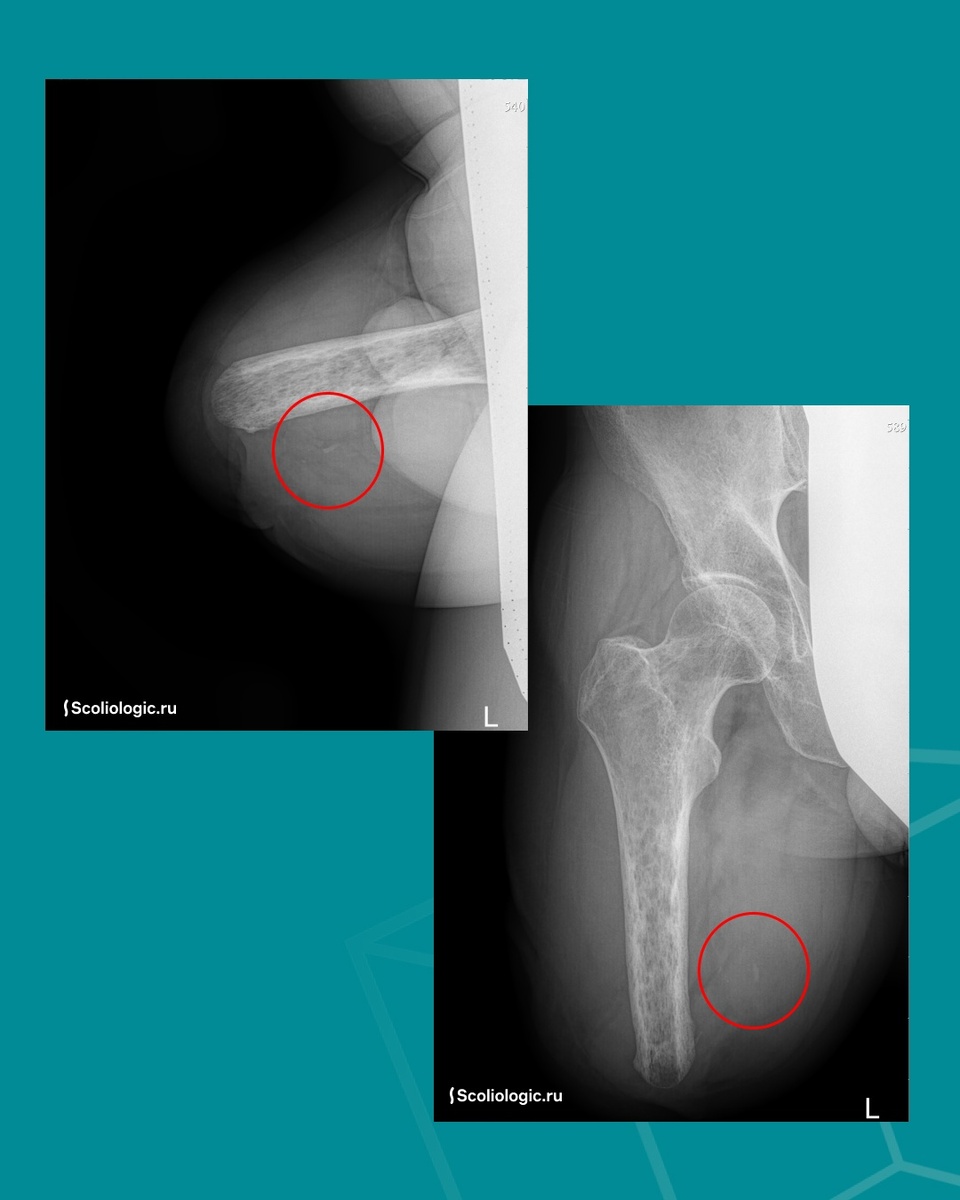

Но врачи отправили пациента на рентген, на снимке обнаружили нечто странное: не похоже на металл, скорее, на кусок пластика. Предположили осколок. Или тромбоз. Отправили на УЗИ. Исследование показало не тромб, а окклюзию – сужение сосуда, приводящее к нарушению кровотока. Хотя полной закупорки не наблюдалось.

Решили оперировать. И оказалось, что внутри – костный

Решили оперировать. И оказалось, что внутри – костный осколок его собственной бедренной кости. Он и сдавливал сосуд, нарушая питание культи. После удаления ситуация стабилизировалась: отёки ушли, нога «успокоилась».